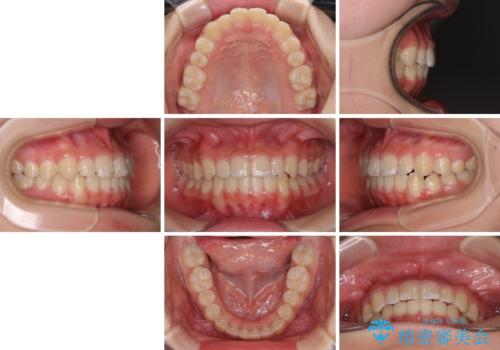

遠方から新幹線で通院 急速拡大装置とインビザラインによる矯正治療

- 急速拡大装置・インビザライン

- 治療計画

- 小児矯正の頃から診察を行っている患者様です。

上顎骨の幅が下顎骨よりも小さいので、拡大装置により骨幅を広げて上下関係を改善し、その後インビザラインにて歯並びを整えることとしました。

上下の骨幅を改善したことで、スムーズに歯列矯正を行うことができました。